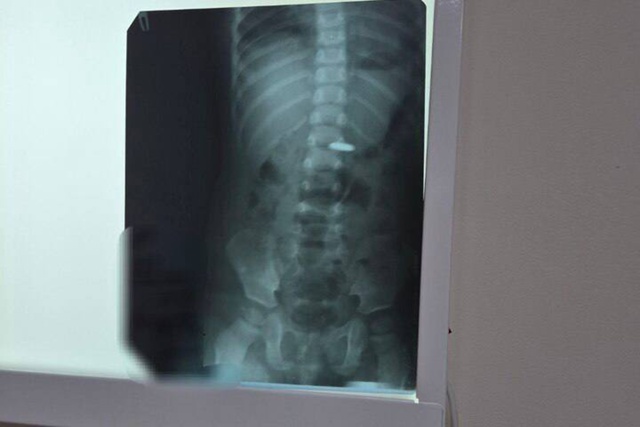

Врачи Балаковской городской клинической больницы спасли годовалого ребенка, который проглотил батарейку. Сообщение об этом появилось в официальном Telegram-канале медучреждения.

Медики призывают немедленно обращаться в стационар, если ребенок проглотил что-то несъедобное. Детский хирург Дарья Гусева она особо подчеркнула смертельную опасность батареек. По ее словам, они наносят мгновенный урон здоровью.

«Попадая внутрь, батарейка вызывает не просто ожог слизистой, но и глубокие поражения тканей, интоксикацию. Разгерметизация с утечкой электролита возможна уже через 2,5 часа, независимо от того, заряжена батарейка или нет», — сообщается в посте.

После рентгенологического подтверждения наличия батарейки в пищеводе или желудке, она незамедлительно удаляется с помощью эндоскопа. В случае проглатывания батарейки большого диаметра, она может застрять в привратнике желудка (месте, где желудок соединяется с кишечником) или зафиксироваться в кишечнике — тогда может потребоваться оперативное вмешательство.